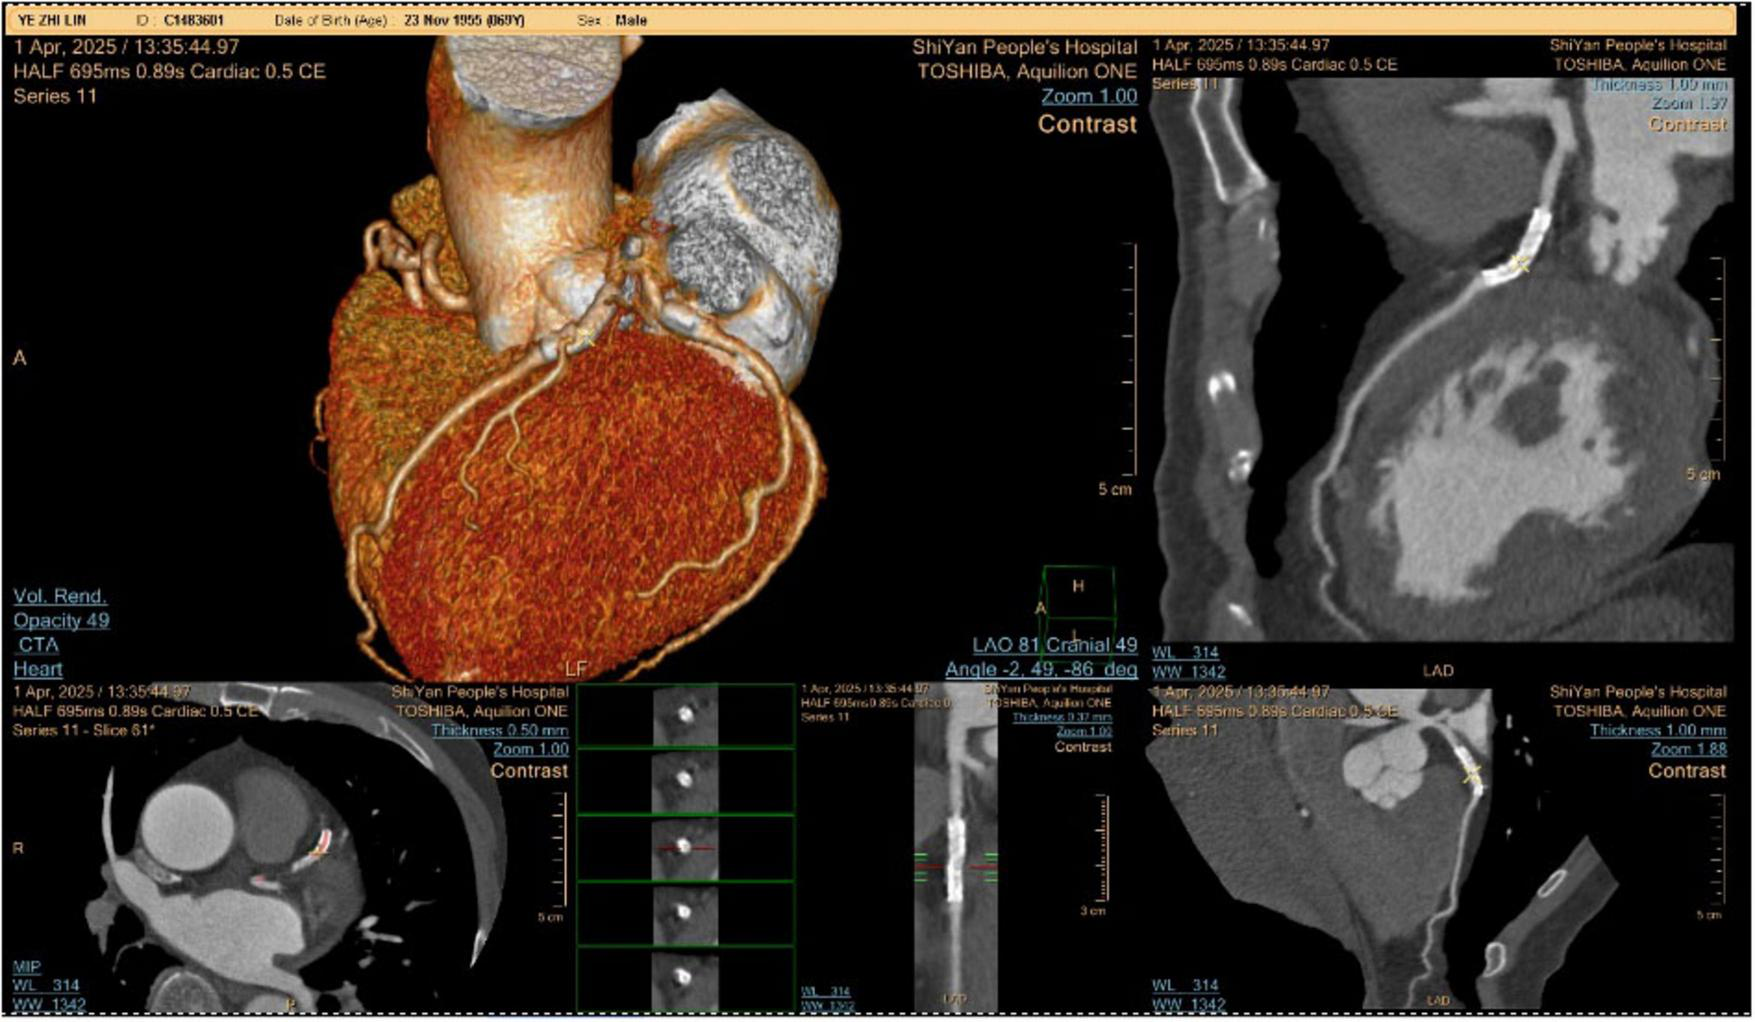

The patient was admitted to the hospital, and a cranial vascular CTA examination revealed cerebral atherosclerosis without obvious vessel stenosis (see Figure 1); a cranial MRI and DWI examination revealed bilateral cerebellar, bilateral frontal-parietal-temporo-occipital, and semiovoid central region infarcts (see Figure 2A); troponin levels were 0.224 ng/ml [ref (ref), 0.0–0.08 ng/ml], Creatine kinase isoenzyme 34 U/L [ref, 0.0–24 U/L], N-terminal brain natriuretic peptide precursor (BNP) 1324 pg/ml [ref, 0.0–300 pg/ml], and an electrocardiogram that suggested an ST-segment abnormality. Cardiovascular consultation was sought to rule out a non-ST-segment elevation myocardial infarction, and antiplatelet aggregation and lipid-modulating therapy were administered. The percentage of eosinophils was 43.4% [ref, 0.4%–8%], and tests for coagulation function, lipids, and liver and renal function revealed no appreciable abnormalities. Two days later, the patient developed severe precordial discomfort and dyspnea. Concurrently, limb muscle strength decreased significantly. On March 31, a physical examination revealed grade 3 muscle strength in the left upper limb, 0 in the right upper limb, and grade 2 muscle strength in both bottom limbs. Figure 3 depicts muscle strength scores provided by the Medical Research Council (MRC). Troponin, creatine kinase isoenzyme, and eosinophil percentage were all steadily declining compared to the prior time frame. As shown in Figure 3, the acidophilic fraction increased steadily. He was moved to the critical care unit (ICU) on March 31 in order to receive correctional treatment. According to a perfect coronary CTA examination, the coronary artery wall had many segmental mixed plaque formation, mild stenosis in the lumen, and an anterior descending branch of the middle section of the stent, which was about 2.3 cm long. The stent did not exhibit any visible fractures or restenosis symptoms, as shown in Figure 4. Bilateral cerebellum, bilateral frontal-parietal-temporo-occipital and semiovarian central area of several spots, and a tiny patchy DWI high signal, measuring between 2 and 18 mm (slightly larger in extent than the previous MR 2025.03.27), were all suggested by the review of the cranial MRI test (see Figure 2B). On April 1, tests revealed a considerably higher eosinophil level. Eosinophilia was discovered following a consultation with the hematology department. To decrease eosinophils, methylprednisolone sodium succinate was administered first, followed by clopidogrel to limit platelet aggregation and low molecular weight heparin for anticoagulation. A bone marrow aspiration was performed to assess flow cytometry, FISH, and fusion genes. Figure 5A shows the flow cytometry results for April 5: an elevated eosinophil percentage. According to the bone marrow aspiration report, there were more eosinophils in the bone marrow and peripheral blood images. Figure 5B shows an increase in eosinophils. Fusion gene screening revealed no results for PCM1:JAK2, ETV6:JAK2, FLT3, ETV6:ABL1, and BCR:JAK2. FISH probe analysis: FGFR1, PDGFRA, and PDGFRB: negative. Low molecular heparin anticoagulation, clopidogrel antiplatelet aggregation, and eosinophils were all reduced by methylprednisolone sodium succinate. Eosinophil counts in the patient progressively returned to normal. The patient’s limb muscle strength improved between 4 and 11; both upper and lower limb muscular strength were grade 3 and grade 4, respectively. He was sent to the rehabilitation department for therapy, and on April 28, he was released from the hospital on June 1. The outpatient follow-up assessment showed that the patient’s limb muscle strength had restored to normal.

FIGURE 4

Coronary CTA examination.